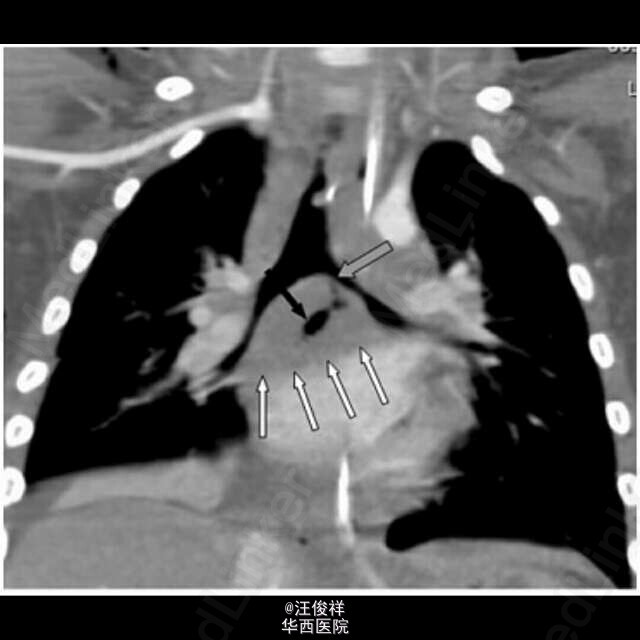

以皮下气肿为症状的结核病很罕见,在儿童中往往见于粟粒性肺结核的病人。 一个26月大的男孩子因为颈部,面部,躯干上半部分肿胀数小时数入院。触诊发现皮下气肿,呼吸系统检查发现左胸壁的爆裂音,但是没有纵膈偏移。胸部平片示:左肺门扩大伴有纵膈积气和广泛的皮下气肿。支气管镜检查排除了异物吸入的可能,但是显示左主支气管被干酪样物质部分阻塞和肉芽肿的明显表现。增强CT示皮下气肿和纵膈积气,双侧肺门淋巴结病变穿透了邻近组织,左主支气管壁严重受损,空气进入皮下和纵膈。结核菌素试验和支气管和胃液PCR实验均证实结核杆菌阳性。给予抗结核治疗后病情好转。